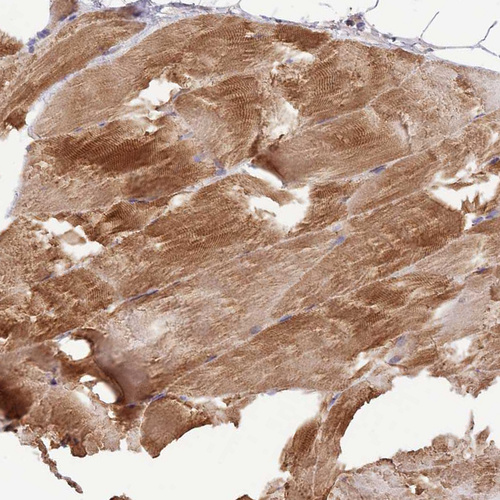

Immunohistochemical staining of human skeletal muscle shows strong cytoplasmic positivity in myocytes.